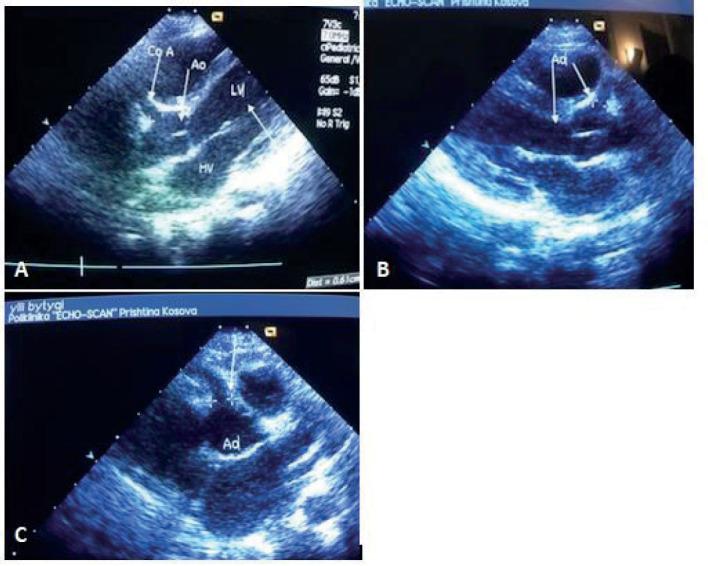

Two adolescent children presented with a toxic shock-like illness, and were subsequently diagnosed with Kawasaki disease shock syndrome when coronary artery abnormalities were found on transthoracic echocardiography.

两名青少年儿童出现中毒性休克样疾病,经胸超声心动图发现冠状动脉异常后,随后被诊断为川崎病休克综合征。